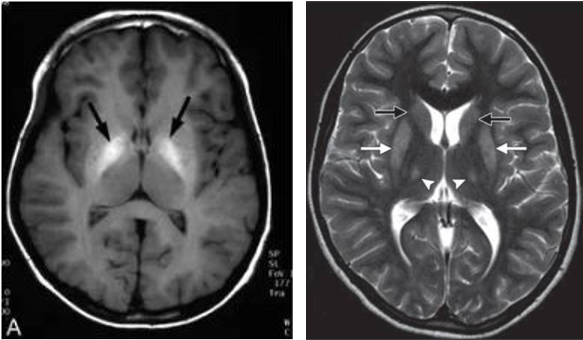

3.头颅影像学:头颅磁共振检查可以看到双侧对称分布的位于豆状核、基底节的病灶。